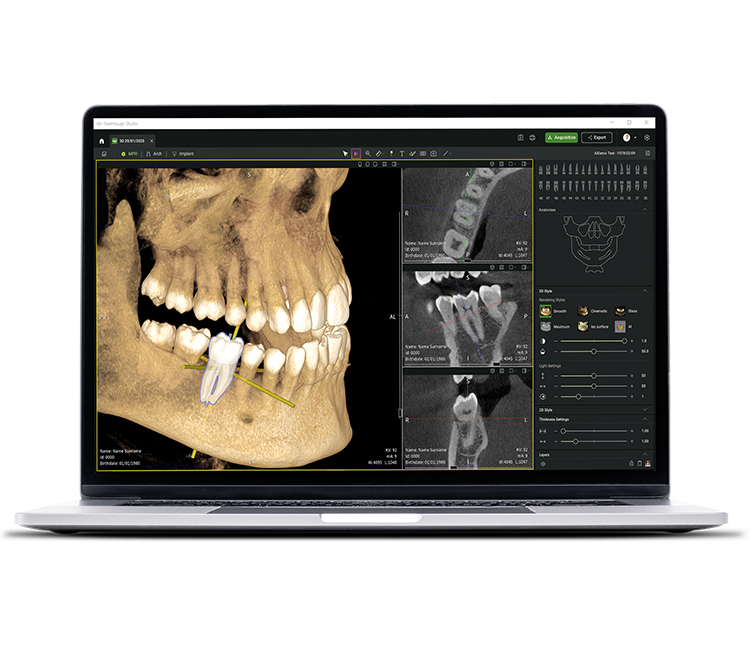

• Seethrough Studio

Yeni seviyeyi gör. Geleceği gör.

Gelişmiş donanım teknolojilerinin yanı sıra, devrim niteliğindeki Seethrough Studio yazılımı, W&H görüntüleme portföyünün yüksek standardının belirleyici bir faktörüdür. Kullanışlı özellikleri ve gelişmiş yapay zeka özellikleriyle Seethrough Studio, görüntüleme kalitesini ve dijital diş hekimliği iş akışlarını yeni bir düzeye taşıyan hepsi bir arada bir çözümdür.

Entegre implant planlama aracı

Seethrough Studio, olağanüstü görüntü kalitesi ve sezgisel kullanımının yanı sıra, tedavinin kolay görselleştirilmesi ve hazırlanması için standart entegre implant planlama aracı gibi birçok kullanışlı özellik sunar.

Yapay zeka fonksiyonları

Seethrough Studio, görüntü iyileştirme için 3D hacim hizalama, diş segmentasyonu, kemer çizgisi oluşturma, otomatik sinir izleme ve patoloji tespiti için yararlı destek dahil olmak üzere çeşitli AI araçlarını kullanır.